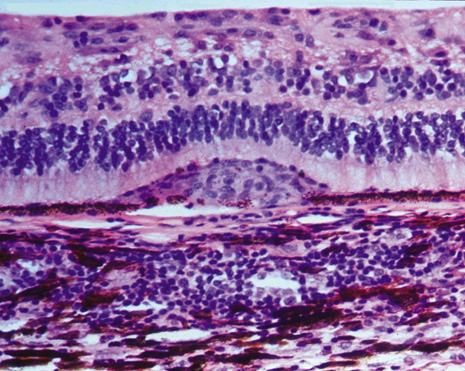

The classic histopathologic features of SO were first described by Fuchs in 1905,3 confirmed by Easom and Zimmerman,63 and summarized by Green.64 Both the injured and the sympathetic eyes show similar histopathologic features. The main feature of SO is a diffuse, non-necrotizing, granulomatous inflammation in the uvea. The choroid is markedly thickened and infiltrated by lymphocytes and nests of macrophages, epithelioid cells, and giant cells. Other classic histopathologic findings include a relative lack of retinal involvement, sparing of the choriocapillaris, and the formation of Dalen-Fuchs nodules, consisting mainly of epithelioid cells located between Bruch's membrane and the retinal pigment epithelium (Fig. 2). Fuchs3 found that approximately 25% of his classic cases of SO had Dalen-Fuchs nodules.

Fig. 2. Microphotograph of Dalen-Fuchs nodule composed of mainly epithelioid histiocytes (macrophages) and a few degenerative pigment epithelial cells between the retinal pigment epithelial cell layer and Bruch's membrane.